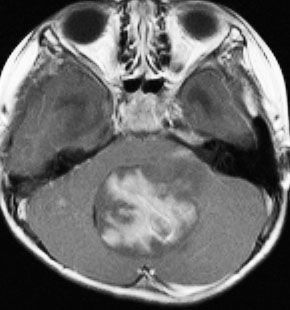

- MRIで診断します

- 境界がはっきりした腫瘍です,くりんとしています

- ガドリニウム造影剤で白く映ります(増強される)

典型的な小脳虫部(小脳の真ん中)の髄芽腫です。横の方,ルシュカ孔へ伸びていないので上衣腫と区別できます。ガドリニウムという造影剤で白く写っています。

- この中にグループ3が含まれています,group 3は髄芽腫の25%ほどを占めるもので乳幼児,男児に発生率が高いです。髄芽腫の中でも最も死亡率が高いものです。組織診断はclassicあるいはanaplasticで,高頻度にMYC増幅あるいはisodicentric 17qがあります。MRIでは小脳虫部発生で腫瘍境界がはっきりしないことがあり,ガドリニウムで強く増強されます。発症時から3割くらいの例で播種が認められます。